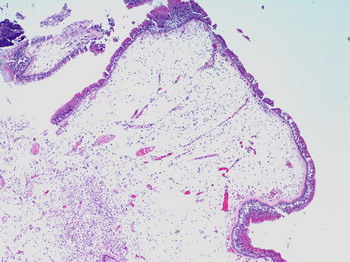

| I-3

Pólipo nasal de carácter inmunoalérgico

(edema intersticial) |

Se

trata de una lesión polipoide múltiple que puede afectar

tanto a las fosas nasales como a los senos paranasales. A menudo

aparece macroscópicamente como “bolsas” o “vesículas”

de contenido acuoso y que reconocen en su fisiopatología

un mecanismo de producción inmunoalérgico. Aparecen

revestidos en su superficie por un epitelio mucoso de tipo respiratorio.

En su estructura interna existe un marcado edema intersticial con

amplios acúmulos de material hídrico a nivel interstical

al que se asocia un componente inflamatorio variable con frecuente

presencia de leucocitos eosinófilos.